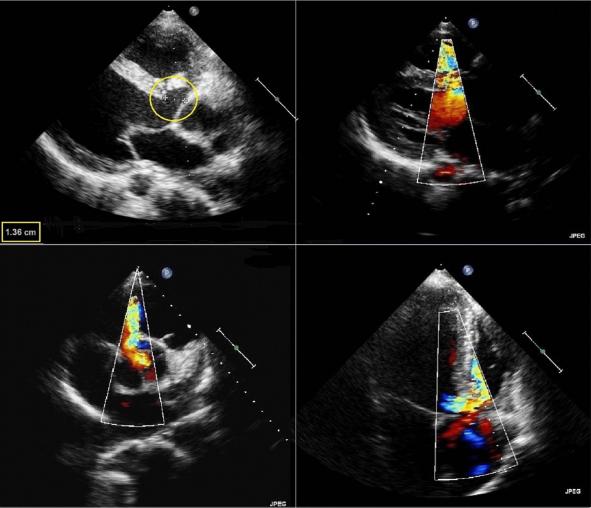

胸部X光显示心脏轮廓增大,提示左心室肥大。其他临床和实验室检查结果在正常范围内。经胸超声心动图显示膜周VSD、中度限制性分流(Qp/Qs=1.6)、AR和升主动脉瘤(图2)。经食道超声心动图证实了类似的发现(图3, 4)。

图3、胸骨旁和心尖部室间隔缺损的彩色多普勒显像